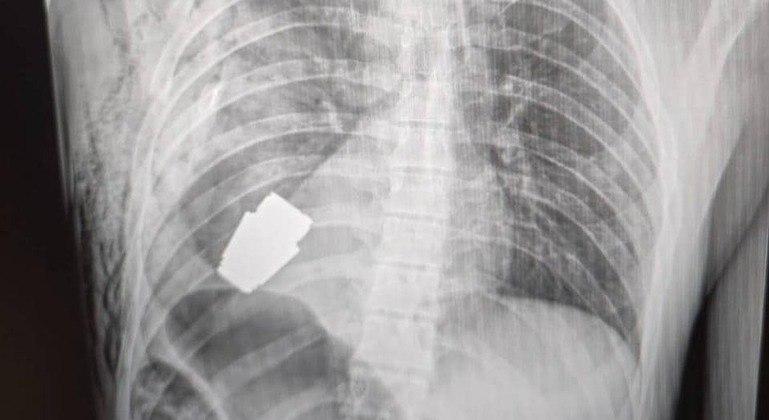

Em sua página no Facebook, o Comando das Forças Médicas das Forças Armadas da Ucrânia compartilhou a imagem de uma radiografia que mostra a granada alojada no peito do soldado.